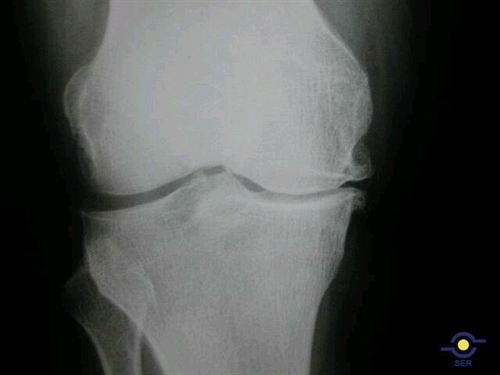

Expertos defienden el uso de fármacos Sysadoa dentro de la primera línea de tratamiento de la artrosis

Por |2019-11-22T19:38:57+02:00septiembre 24th, 2013|Alimentación, Cirugía, Enfermedades, Esqueleto, Investigación, Nutrición, Ortopedia|Comentarios desactivados en Expertos defienden el uso de fármacos Sysadoa dentro de la primera línea de tratamiento de la artrosis

artrosis-rodilla

La artrosis es una patología crónica que afecta a más de 7 millones de pacientes en España; debido a que es dolorosa y discapacitante, y tiene el condicionante del desgaste progresivo […]